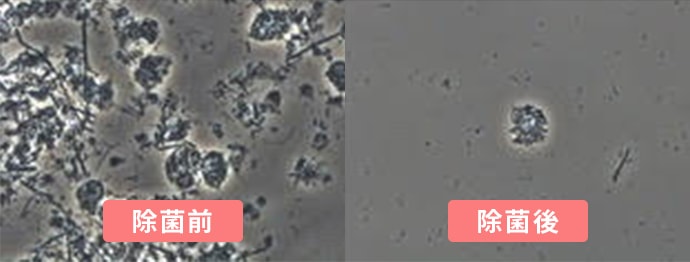

-

薬で治す歯周内科治療

重度の歯周病は、歯石取りをしても感染が収まらないことがあります。お薬を使った治療なら、歯周病菌の感染を抑えて徹底的な除菌が可能です。